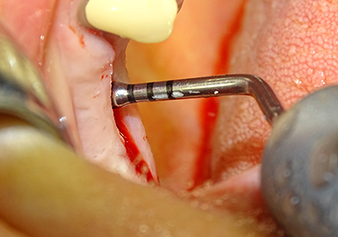

Following an intermediate check (Fig. 4) a further preparation step was performed (Fig. 5). Afterwards, the hydraulic Z35P instrument was used to lift the membrane to the desired position (Fig. 6 and 7). This was followed by further piezosurgical preparation of the implant bed, concluded with a rotary bur and shoulder milling cutter up to the implant diameter of 4.8 mm. Before the implant was inserted, the augmentation material (particle size approx. 0.8-1.6 mm) was introduced underneath the Schneiderian membrane (Fig. 8).

Implantation and prosthetic restoration

To move the augmentation material in the direction of the maxillary sinus atraumatically, the implant was inserted very slowly by hand (Fig. 9). In the process, the membrane was pushed in the cranial direction once again. After two months, the surgical site healed without irritation. Six months later, the x-ray check showed a significant increase in opacity as an indication of ossification (Fig. 10). The prosthetic restoration was carried out with a metal-ceramic crown.